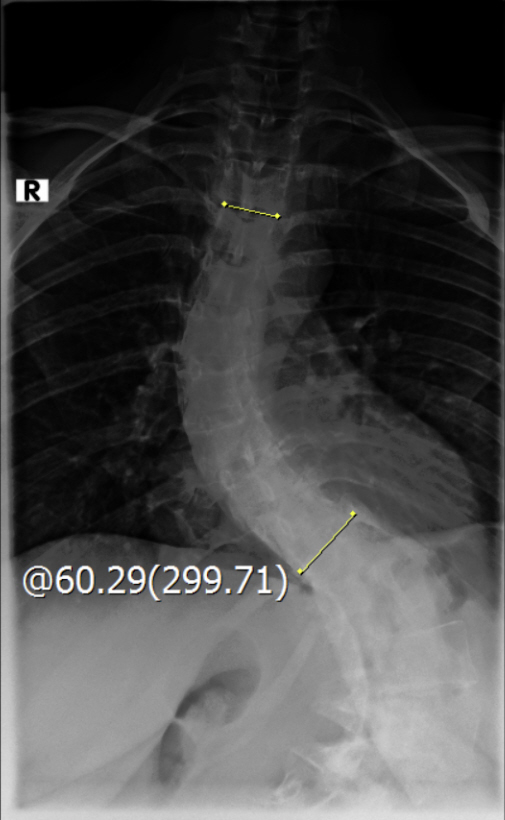

Thorakolumbalskoliose mit aktuellen COBB-Winkeln von 80 und 60 Grad...wenig Schmerzen und daher meistens glücklich

Viele kennen sich aus, daher möchte ich euch meine aktuellen Röntgenbilder nicht vorenthalten und hänge sie unten an.

Ich war beim MVZ Gersthofen, dort wurden die Röntgenbilder gemacht…die massive Verschlechterung war sehr offensichtlich

Dort wurden die Winkel gemessen, unten 80 Grad und oben 60 Grad…eine Verschlechterung von über 2 Grad pro Jahr, wenn man es auf die ganze Zeit berechnet

Die Winkel hab ich nachgemessen, wie der Arzt der Hessing und hier mal als Screenshot